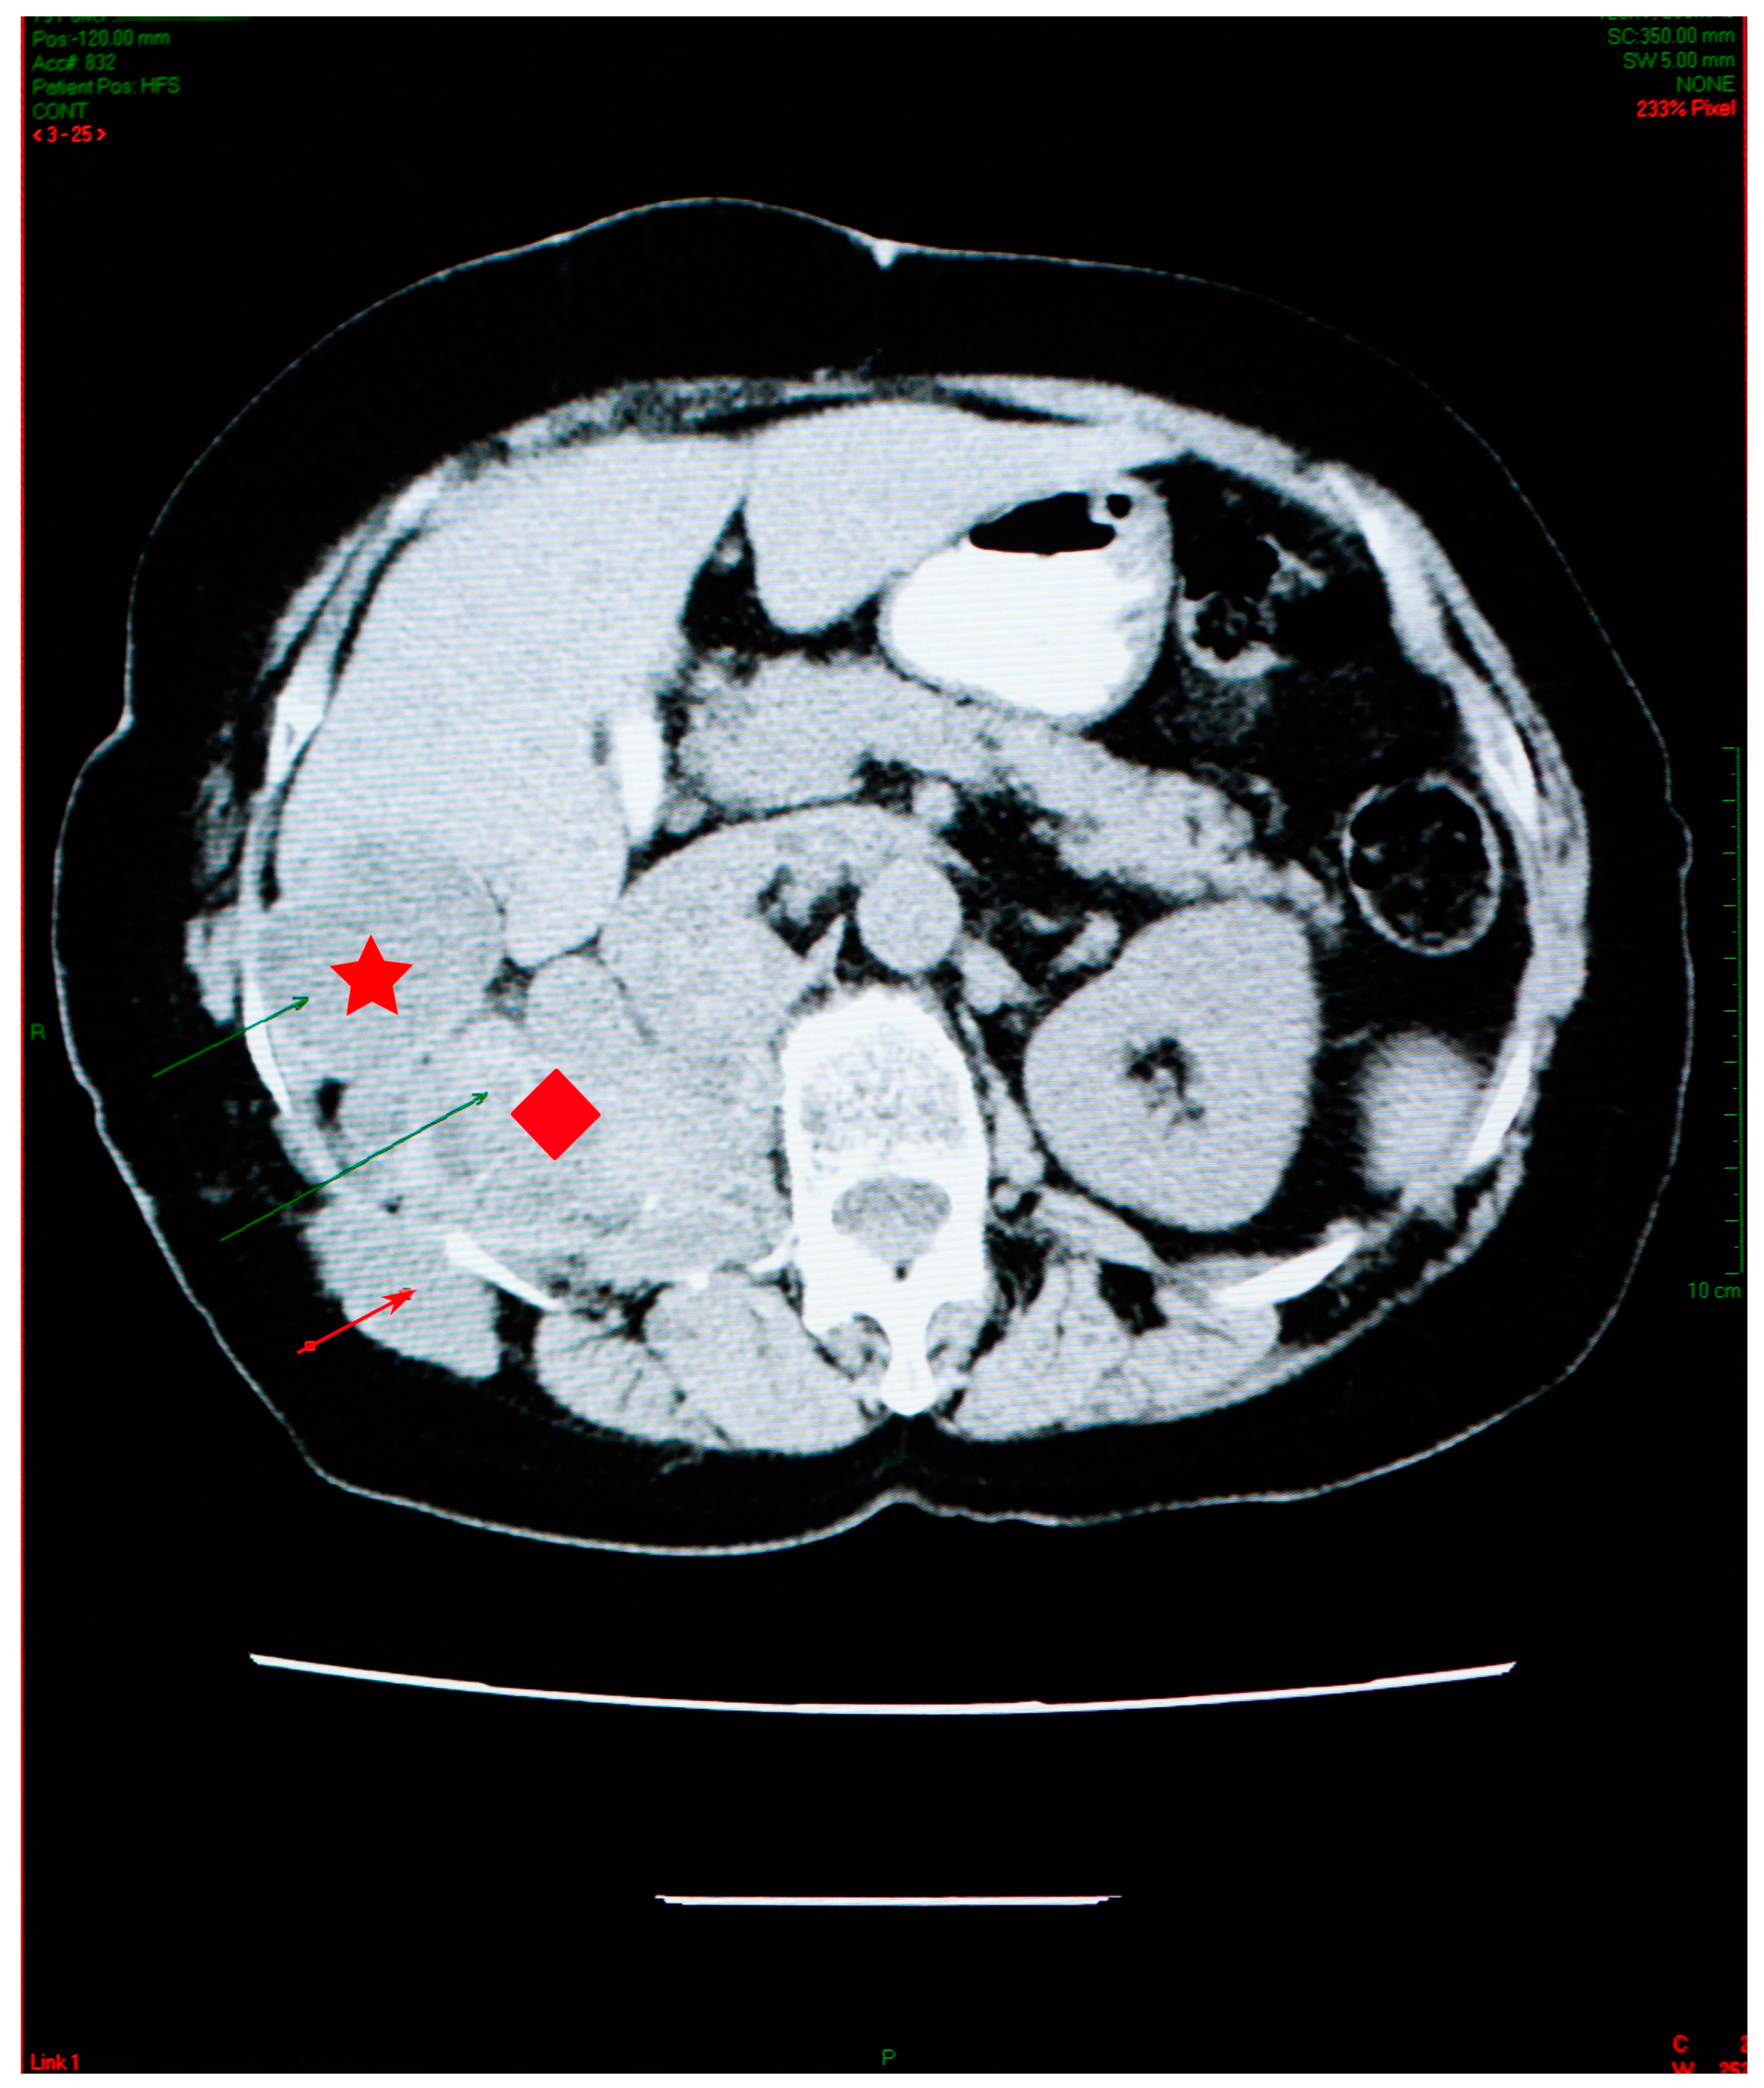

Abdominal imaging revealed multiple cysts, with lots of septa, confluent in the right kidney space, invading the retroperitoneal area down into the right pelvic region, situated between the aorta and the vena cava. Similar types of damage were visible in the sixth right liver segment, as well as the right iliac fossa, and the right paravertebral region (Figure 3).

The right kidney could not be visualized. The psoas muscle, along with the spaces between intestinal loops, had been infiltrated by the same sort of septate cystic masses. A somewhat larger mass, with a size of 45/33 mm, was observed adjacent to the bowel on the right side. The specific serology was intensely positive.

The abdominal CT scan showed multiple spontaneous hypodense masses with hyperdense borders, occupying the entire kidney space, with no evidence for the right kidney (Figure 6).

The maximum axial dimension of the above-mentioned lesions was 10 cm, which is considerably less than what was recorded in 2006. In addition, this conglomerate of hypodense images was remarked to have increased in overall density. The conglomerate presented cranial and caudal extension, starting just beneath the diaphragm and ending right under the plane of the renal artery, with a close anatomic relation to the right diaphragm pillar, right hemidiaphragm, and right psoas muscle. The spontaneous hypodense, heterogenous mass, with an axial maximum diameter of 46 mm, located in the VI liver segment, appeared to be reduced in comparison to the 2006 examination.

Figure 3. Abdominal CT scan showing multiple cysts, confluent in the right kidney space (red diamond), invading the retroperitoneal area, in the sixth right liver segment (star) and in the right iliac fossa and right paravertebral area (arrow).